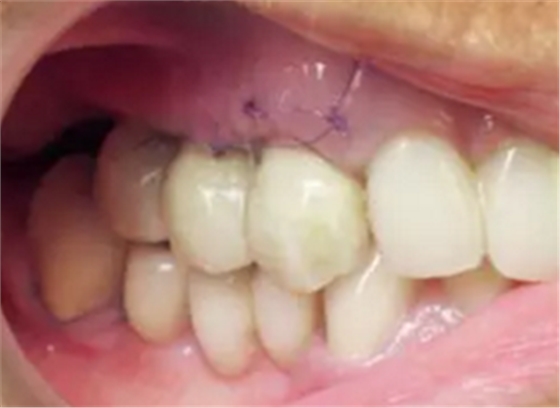

將腭側(cè)牙齦部分剝離形成帶蒂瓣來(lái)重建齦乳頭。通過(guò)縫合固定牙齦位置(圖18)。螺絲固位的兩段式CAD/CAM橋在術(shù)前準(zhǔn)備好,術(shù)后即刻放置并使用螺絲固位于種植體上(圖19,20)。螺絲固位過(guò)程施以略大扭力,但這對(duì)種植體沒(méi)有任何影響,因?yàn)榉N植體尚未完成骨整合,并且機(jī)械壓力很小。這樣做是為了輕微改善臨時(shí)橋在咬合狀態(tài)的適應(yīng)能力。

圖18

圖19

圖20

另外,SLA表面可以吸附血漿中的蛋白質(zhì),,并促進(jìn)纖維網(wǎng)狀結(jié)構(gòu)的形成從而加速骨成熟。這對(duì)于拔牙后即刻種植并即刻改善美觀(guān)的治療方式來(lái)說(shuō)是一個(gè)巨大的優(yōu)點(diǎn)。術(shù)后10天(圖21)和4周(圖22)復(fù)查,明確牙齦恢復(fù)狀態(tài)和種植體結(jié)合情況。術(shù)后沒(méi)有出現(xiàn)疼痛、水腫或血腫的情況。

圖21